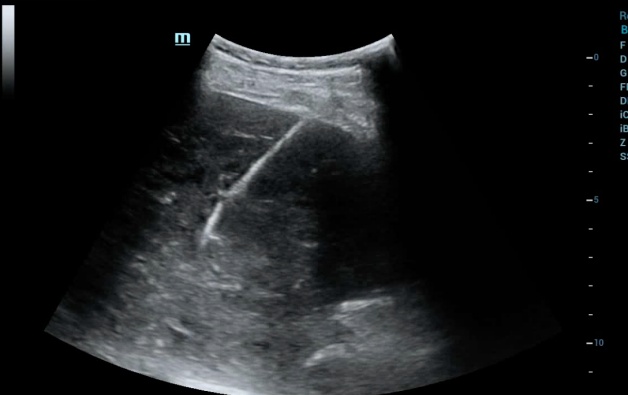

经过数天抗感染治疗,ct复查示脓肿持续增大,白细胞居高不下,肝肾功能出现异常,为了防止病情进一步发展,普外科与超声医学科陈曼主任会诊后认为急需进行超声引导下肝脓肿穿刺置管引流,需要对抽出的脓液进行细菌培养和药物敏感试验,以便选用有效的抗生素进行治疗,同时置管引流脓液。

术前对病灶进行充分评估,并做了超声造影,肝脓肿较成人拳头略大,內见较多的分隔。

于是,我们决定进行肝脓肿的置管引流。同时,患者的核酸报告结果也为阴性,在封控的情况下,我们第一次在身穿防护服及三层手套的条件下进行手术,抽出脓液20ml,并顺利完成了置管引流,过程顺利,病人安全。

此项技术是指通过超声评估,确定患者是否满足肝脓肿穿刺的条件、有无进针的安全路径以规避肝内重要管道结构(如肝动脉、肝静脉、肝内胆管及门静脉等)。患者通常局部麻醉,在超声实时监测下,医生可从入皮肤开始,全程直观的观察并操作穿刺针以最安全的路径到达肝脓肿部位,抽吸脓液并置管引流,具有安全、创伤小等优点。